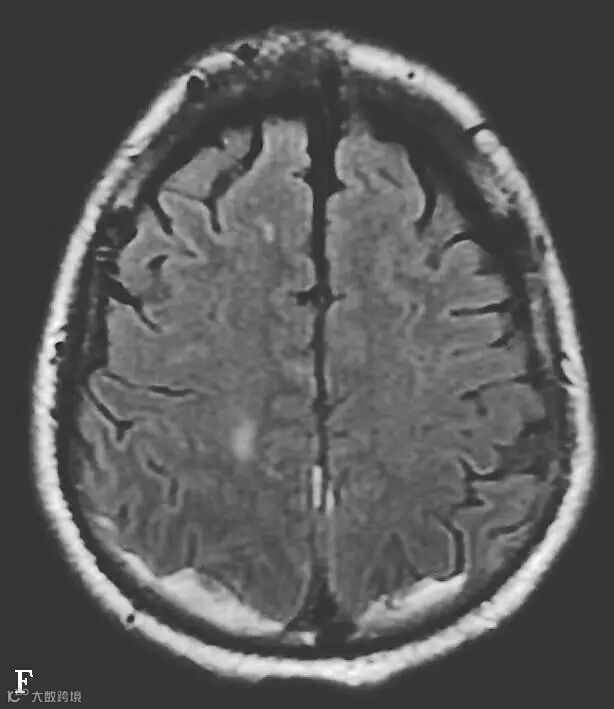

图6-11-1 弥漫性轴索损伤并双侧额部硬膜下积液、双侧顶枕部硬膜下血肿

男,34岁,外伤后7天。A~H(A、B.T2WI,C、D.T1WI,E、F.T2WI-FLAIR,G、H.DWI):左侧岛叶及右侧顶叶白质可见斑片状稍长T1稍长T2信号,边缘不清,FLAIR及DWI呈高信号。双侧额部内板下可见新月形长T1长T2信号,FLAIR及DWI呈低信号。双侧顶枕部内板下可见弧形短T1长T2信号,FLAIR及DWI呈高信号